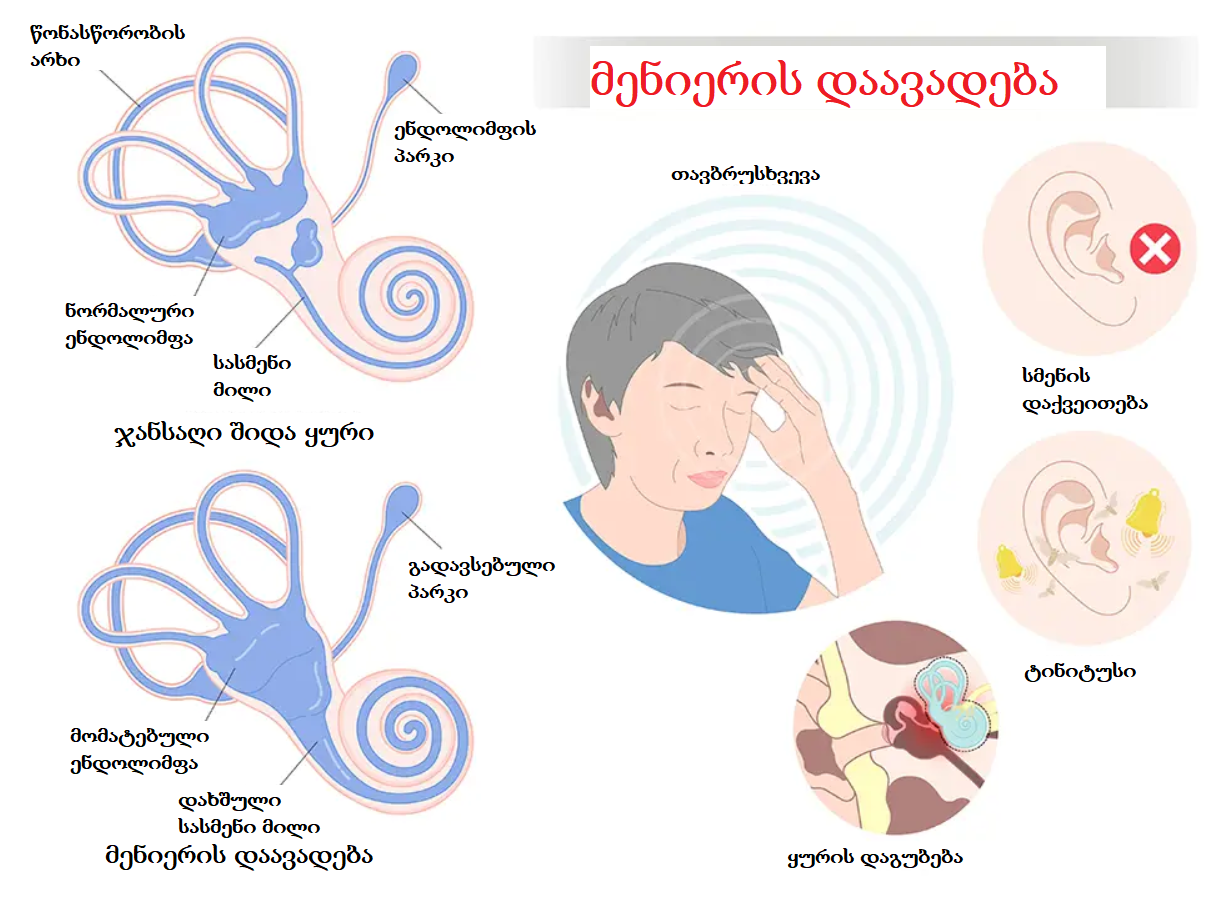

ვერტებრო-ბაზილარული უკმარისობა (VBI) და მენიერის დაავადება ორი განსხვავებული მდგომარეობაა, თუმცა მათ შეიძლება ჰქონდეთ გარკვეული მსგავსი სიმპტომები, რაც ზოგჯერ დიაგნოსტიკურ სირთულეებს ქმნის. მოდით, განვიხილოთ ეს საკითხი უფრო დეტალურად.

ორივე მდგომარეობის დროს შესაძლებელია გამოვლინდეს შემდეგი სიმპტომები:

- თავბრუსხვევა (ვერტიგო): ეს არის ერთ-ერთი ყველაზე გავრცელებული სიმპტომი ორივე დაავადებისთვის. თუმცა, თავბრუსხვევის ხასიათი და ხანგრძლივობა შეიძლება განსხვავდებოდეს.

- წონასწორობის დარღვევა: ორივე შემთხვევაში პაციენტებს შეიძლება ჰქონდეთ სიარულის გაძნელება, არამდგრადობის შეგრძნება.

- ტინიტუსი (ყურებში ხმაური): ზოგჯერ ორივე მდგომარეობას შეიძლება ახლდეს ყურებში ხმაური.

- გულისრევა და ღებინება: თავბრუსხვევის ძლიერი ეპიზოდების დროს შესაძლებელია გულისრევა და ღებინება ორივე დაავადების შემთხვევაში.

ძირითადი განსხვავებები ვერტებრო-ბაზილარულ უკმარისობასა და მენიერის დაავადებას შორის:

მიუხედავად გარკვეული მსგავსებისა, არსებობს მნიშვნელოვანი განსხვავებები, რომლებიც ხელს უწყობს დიაგნოზის დიფერენცირებას, ნახეთ ცხრილი:

მიუხედავად იმისა, რომ ვერტებრო-ბაზილარულ უკმარისობასა და მენიერის დაავადებას შეიძლება ჰქონდეთ საერთო სიმპტომები, როგორიცაა თავბრუსხვევა და წონასწორობის დარღვევა, ისინი ფუნდამენტურად განსხვავდებიან გამომწვევი მიზეზებით, სიმპტომების კომპლექსით, მიმდინარეობითა და დიაგნოსტიკური მიდგომებით.